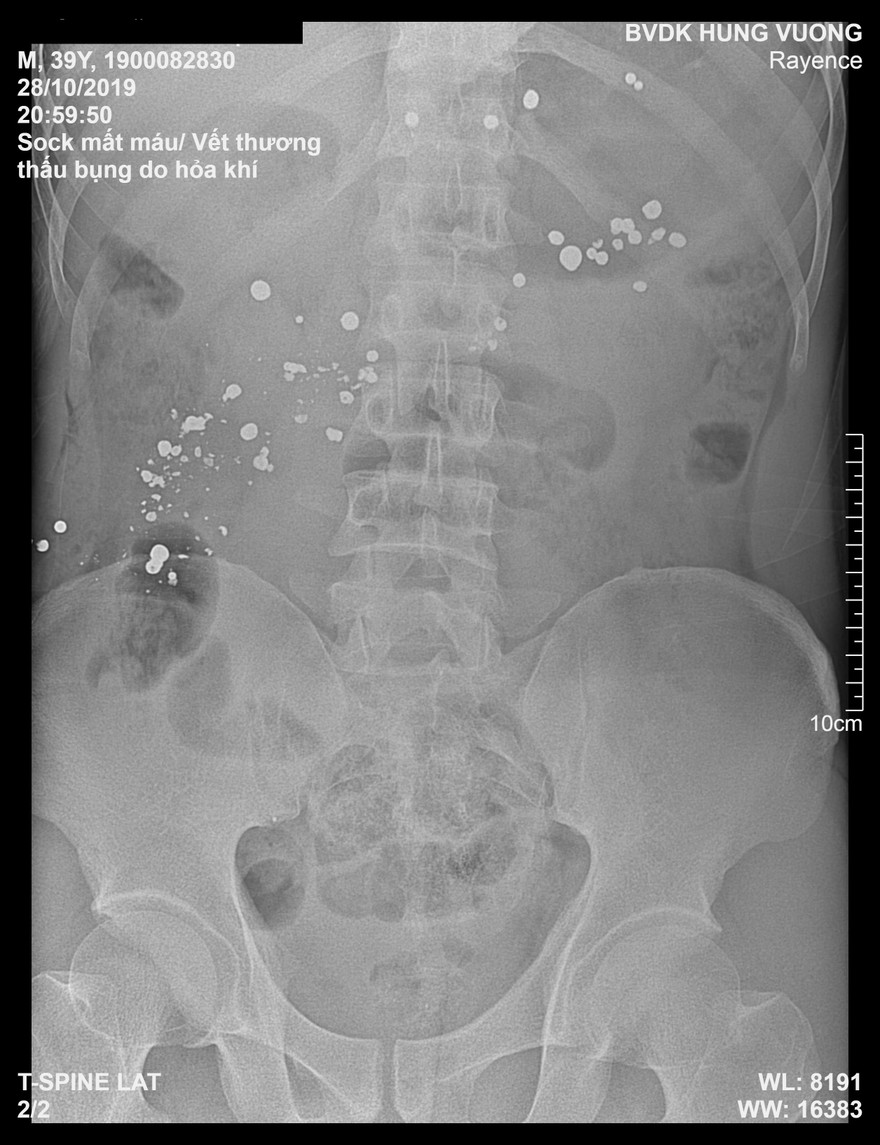

Ảnh chụp X quang bệnh nhân có nhiều dị vật kim khí cản quang trong ổ bụng.

Qua hệ thống chụp X Quang và chụp cắt lớp, các bác sĩ chẩn đoán hình ảnh phát hiện có rất nhiều dị vật kim khí cản quang trong ổ bụng, mạn sườn trái và vùng khung chậu, và ra y lệnh mổ cấp cứu và truyền máu ngay lập tức. Trong quá trình thực hiện mổ cấp cứu, bệnh nhân đã được truyền 4 đơn vị máu.